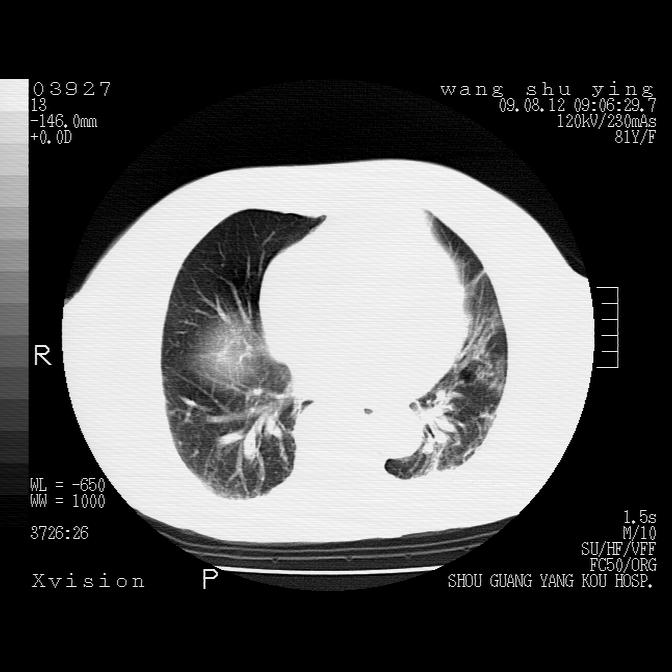

以下是引用帅河马在2009-8-12 12:59:00的发言:[br]两肺感染性病变伴双侧胸膜肥厚。[br]左侧甲状腺腺瘤不除外。[br]腹水+心包积液。[br][br][本贴已被 帅河马 于 2009-8-12 13:14:32 修改过]

以下是引用sdzyy在2009-8-12 18:17:00的发言:[br]两肺感染性病变伴双侧胸膜肥厚。[br]左侧甲状腺腺瘤不除外。[br]腹水+心包积液。[br]支持

以下是引用随光逐影在2009-8-12 19:42:00的发言:[br]1)两肺感染性病变伴双侧胸膜肥厚。2)不排除左侧甲状腺腺瘤。3)肝脏占位性病变;建议行进一步检查。